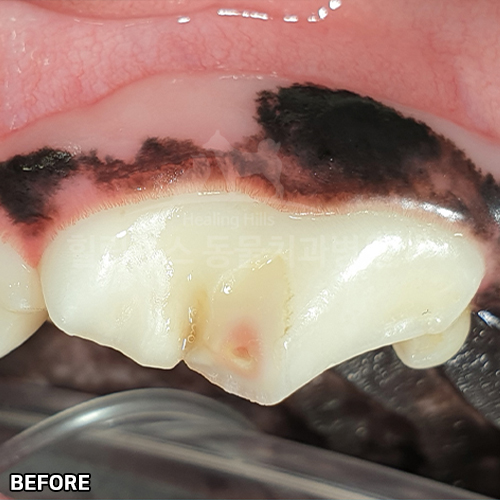

[강아지 치아파절 치료 후 4년 경과모습]

샘플